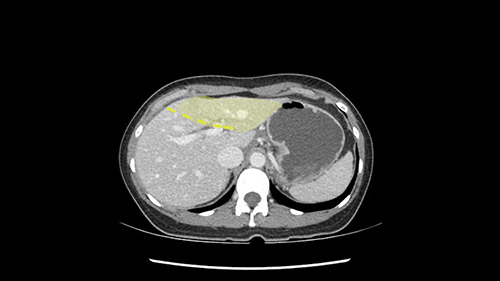

So if we look at the CT scan, on the axial, it’s a larger lesion. It’s about 6 or 7 or 8 centimeters. So it does look a bit threatening in terms of its resectability but if you really drill down deeply into the anatomy, and I think the coronal [imaging] is even better, you can see that the entire mass is on the patient’s left side of the falciform ligament. So it’s really only a left-sided tumor and not even really a left-sided tumor because Segment 4 is uninvolved anatomically.

None of the parenchyma is affected and this tumor is very exophytic; like many Hepatitis B hepatomas; and otherwise is resectable with either a wedge resection part of Segment 2-3 or a formal left lateral segmentectomy.

As I review the CT scan, we have both arterial and venous phases, the tumor is obvious. But I’ll start by saying that the liver itself does not appear to be cirrhotic to my eye. It’s got a normal contour and allied to that, that I do not see evidence of portal hypertension. The spleen is normal, there’s no collateral vessels. The tumor itself, I measured maximally at about 11 centimetres in diameter and I’m told the alpha fetoprotein is very high (over 10000), which is entirely consistent with this being a solitary hepatocellular carcinoma that is very exophytic. It seems to emanate off the inferior margin of Segment 3 (because that’s the falciform). I’ll start by saying that this is not transplantable. The tumor exceeds our guidelines for transplantation, but it's likely resectable based on normal liver and no portal hypertension.

When you see the axial sections of the scan, you find it's a largely exophytic mass and its well-encapsulated. So this is typically true of a well-differentiated hepatocellular carcinoma. If you look at this, this is the gallbladder which is being displaced to the right and the mass is in the Sg4 of the liver, exophytic, projecting down. As it is coming down, it is also displacing the duodenum and the head of the pancreas which is being pushed towards the left and it's going right up to the cava, the start of the anterior surface of the cava. Obviously getting a lot of collaterals and vascularity from all the vessels around but one has to be very careful in evaluation of the main portal pedicle in this particular case and of course arterial inflow to the Sg4 and of course the left lobe of the liver.

What kind of procedure can we plan for this patient? It obviously has to be a left hemihepatectomy because most of the lesion is actually in Sg4. Can we do something which is less than a hemihepatectomy and just do only a segmental resection? The answer to that is that this vascular supply, if you are trying to ligate only the portal venous pedicle to the Segment 4, it is very close to the tumor and you will end up not having not a great margin as far as tumor resection is concerned so I would recommend a left hemihepatectomy and not just a partial or segmental resection. You can also see that it is crossing the falciform line and going on to Segment 2 and 3 so trying to do anything less than a left hemihepatectomy may not give the right kind of margins which we need for this tumor. Fortunately for us, the contours of the liver, which are very important to see in a Hepatitis B patient, there are no cirrhosis which I can see. The normal liver functions indicate that it's a well compensated Hepatitis B.